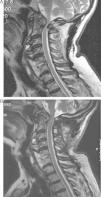

The authors present the case of a 76-year-old man previously diagnosed with diffuse idiopathic skeletal hyperostosis who presented with severe progressive myelopathy. A magnetic resonance imaging of his cervical spine revealed a retro-odontoid predural mass, which caused a severe compression of the cervical spinal cord. The patient underwent a posterior laminectomy of the atlas and an occipitocervical fusion. After surgery, the pseudotumor was considerably smaller and the neurological symptoms improved.